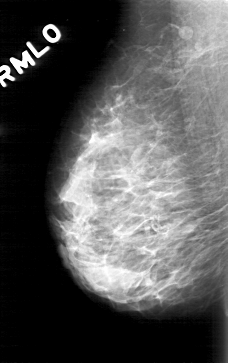

D_4171_1.RIGHT_MLO

RIGHT_MLO LINES 5071 PIXELS_PER_LINE 3181 BITS_PER_PIXEL 12 RESOLUTION 43.5 NON_OVERLAY